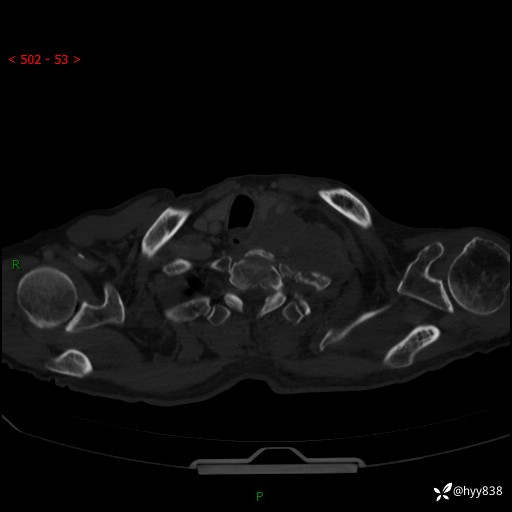

老年男性,气促5月,胸背痛2月。发现肺尖较大肿块,摧枯拉朽之势---结果公布~

现病史:患者于5月前饮酒后突发静息状态下气促不适,无胸闷、胸痛、发热、咳嗽、咳痰等不适,于当地第五人民医院及我院就诊,输液治疗后(具体不详)后气促稍缓解,遂出院后自行口服中草药治疗。近2月出现胸背痛,伴左上肢疼痛、乏力、感觉异常,稍有咳嗽、咳痰,咳黄痰、痰液粘稠,无咳血。为进一步诊治来我院。

胸部CT增强扫描(外院平扫)